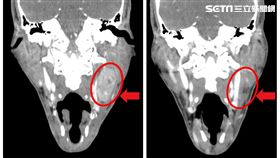

扁桃腺癌轉移淋巴 陳凱倫冒1腫塊疑復發

陳凱倫近來舉辦3場「金曲傳愛壯世代公益演唱會」,為此...

陳凱倫證實罹癌轉移至淋巴!緊急重大手術

藝人陳凱倫三年前罹患扁桃腺癌,並已轉移至淋巴,歷經兩...

扁桃腺癌擴散淋巴 陳凱倫化療續命現狀曝

67歲3屆廣播金鐘獎得主陳凱倫2022年11月被診斷...

陳凱倫扁桃腺癌!6症狀是警訊 確診常晚期

知名主持人陳凱倫,2022年11月被診斷罹患扁桃腺癌...

陳凱倫扁桃腺癌4期 醫:末期半數可治好

66歲金鐘獎主持人陳凱倫於去年11月中因為發現頸部腫...

女左頸冒小腫塊 無症狀竟罹癌第3期

頸部若出現小腫塊千萬不要輕忽!台中有位48歲女子,前...